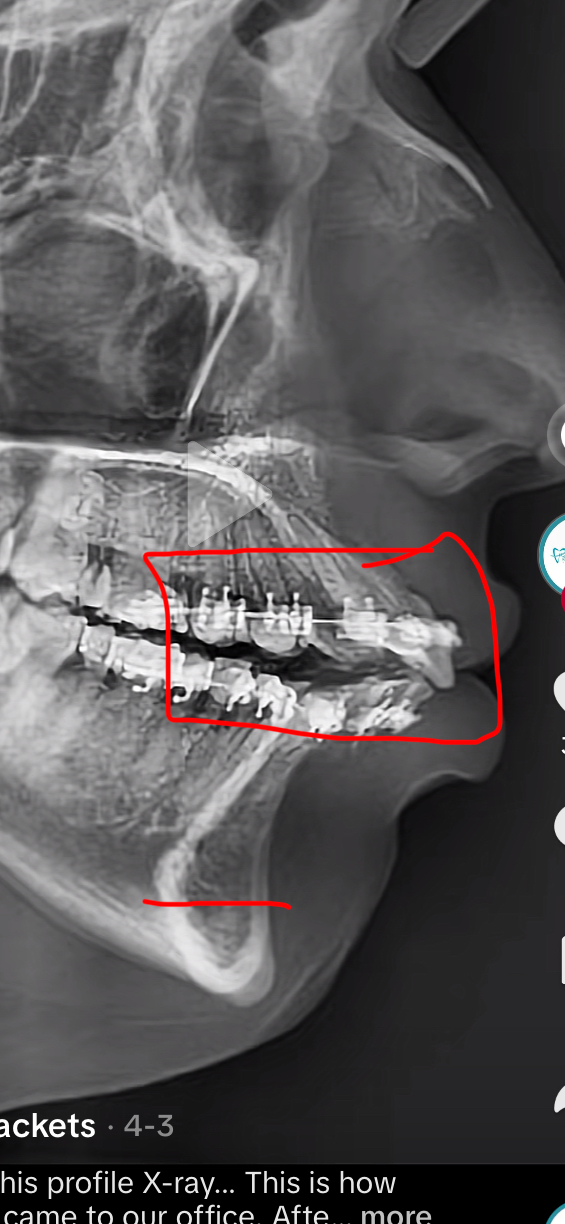

DNR i was just wondering if anyone had experience from it since my teeth would be loose and i was wondering if it would push them out too much too like this or not

IMG 6353